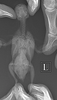

Здравствуйте. Мы все таки доехали до врача и узнали, что в регионе у нас никто не сделает анализы помета. Врач нас отправила на рентген (фото прилагаю), нашли воспаление на грудке, предполагают, что травма. Не знаем, что и делать. Отправляю вам фото.

По поводу еды - ест безостановочно, но мало. Корм его запариваю с кашей детской, чтобы поступала еда, вес поднимался до 38 грамм, сейчас опять 36. 3E8243C1-625E-43C6-B8A9-B2A2D5BAEB15.png 3F798090-A99A-4A11-81BE-4250C6F14E68.png

Неплохо выполнен рентген. Напишите адрес и наименование клиники, и как врача зовут.

По снимку. Ничего хорошего.

1.Оранжевым указала остро увеличенные почки, скорее всего- неоплазия.

2.Зеленым- зона где должна быть нормально печень, а сейчас там муть одна, матовое стекло, возможно- под ней сидят злые семенники . Возможен цирроз на фоне онкопроцесса, или кровоизлияние .

3.Голубым- то ли неоплазия зоба, то ли стороннее включение по типу комка ниток/бумаги.

С учетом 1 и 2- скорее неоплазия.

Итог- неутешительный. Велика вероятность злокачественного новообразования почек или семенников, с MTS в печень и слизистые зоба.